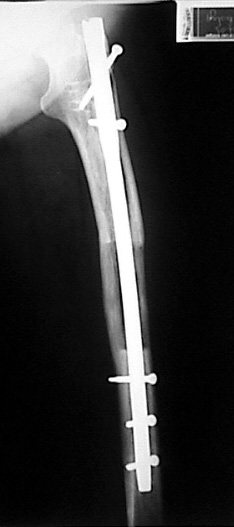

The patient lies is supine position at a traction table and legs are crossed with the uninvolved leg at the bottom. The medullary cavity is penetrated through piriform fossa using the standard method, and medulla is reamed 1.5 mm thicker than the nail to be used, over a guidewire. Proximal femur is reamed more, because the intramedullary nail is thicker proximally. The osteotomy site is planned at the X-Rays. It is important that at least 8 cm. of nail remains distal to the osteotomy site after the completion of the lengthening procedure. Percutaneous corticotomy is performed. The guide wire is advanced distally in order to measure the length of the nail. An intramedullary nail of apropriate length is placed. In the end, the nail is interlocked proximally, a suction drain is placed and the fist step of the operation is completed.

In selected cases, we prefer to use a combination of a unilateral dynamic axial fixator and an interlocked intramedullary nail, in order to protect the length and alignment after the completion of the lengthening procedure. As a prerequisite for this technique, the narowest diameter of the medullary cavity shall be wider than 7 mm and the length of the nail segment distal to the osteotomy site shall be at least 8 cm. after the completion of the lengthening procedure.The intramedullary nail neutralizes shear and bending forces on femur during lengthening, shortens external fixation time, and protects newly formed bone against fractures. In our series, subtrochanteric osteotomy was performed in one case. No varus angulation occured despite the intramedullary nail.